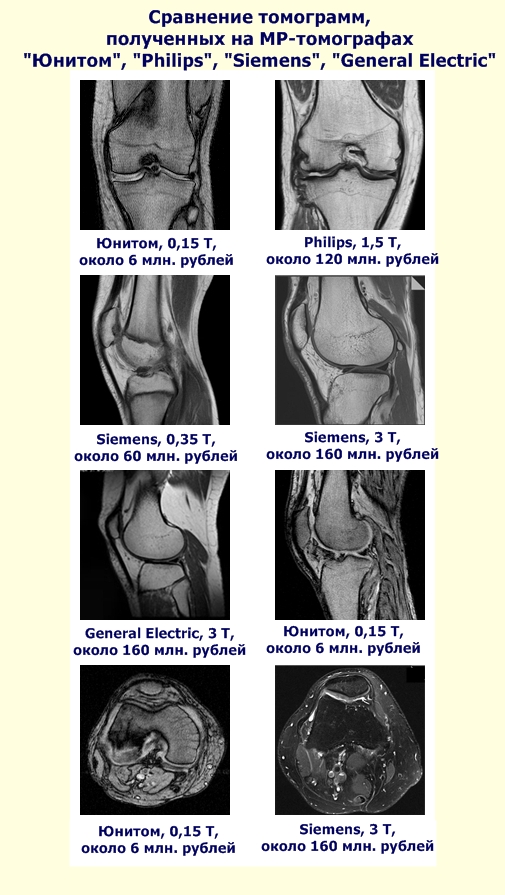

The world's first fully digital magnetic scanner . Suffice it to say that in a second measurement is recorded and processed one billion bits of data in real time. The use of the latest technological advances brought results: obtained image quality is not worse than on costly foreign imagers . Prices of the last times and reach 160 million rubles. The problem of high prices has become known throughout the country thanks to the president's robust language.

Public MRI scanner - scanner "Unitom" - no need for expensive cryogenic materials for his service . He is the most "green" scanner: its power consumption compared to foreign energy high field scanners below 100 (!!!) times. So, scanner can be powered by solar panels, even ! The size of the room where you can set the "Unitom", a fraction of the size of the room required for the traditional foreign MRI. Also, thanks to the many innovative solutions, Public MRI scanner is only 6 million rubles .

Detector "Unitom" has successfully passed the clinical and technical tests, has all the necessary permits, has more than one hundred patients in real practice. received 30 000 tomograms . Numerous advantages of the scanner "Unitom" to foreign analogues confirm eminent scientists, doctors, including SB RAS, MSU, MIPT . Applications for the purchase of the imager "Unitom" are derived from more than 40 countries are negotiating co-production with the Public MRI scanner National Research Council of Canada.

Take our scanner. Many also did not believe in creating it. There is no government funding we have received. But today the scanner already exists and has more than one hundred patients. It should be noted, we did not want to cry about this achievement until you went all the way from idea to put it into practice - that is, until real Clinical operating system. And what we see now? Image obtained by MRI scanner "Unitom", which should become the prototype of the Public MRI scanner, it is not worse than the images obtained by MRI promoted foreign production.

Just look at the captured images, and do all yourself. The problem is that many do not even want to believe your eyes, do not want to believe the facts. So, I talked to one doctor who considers himself a professional in the diagnosis. He did not even look at the pictures that I showed him. That's what worries, to put it mildly...